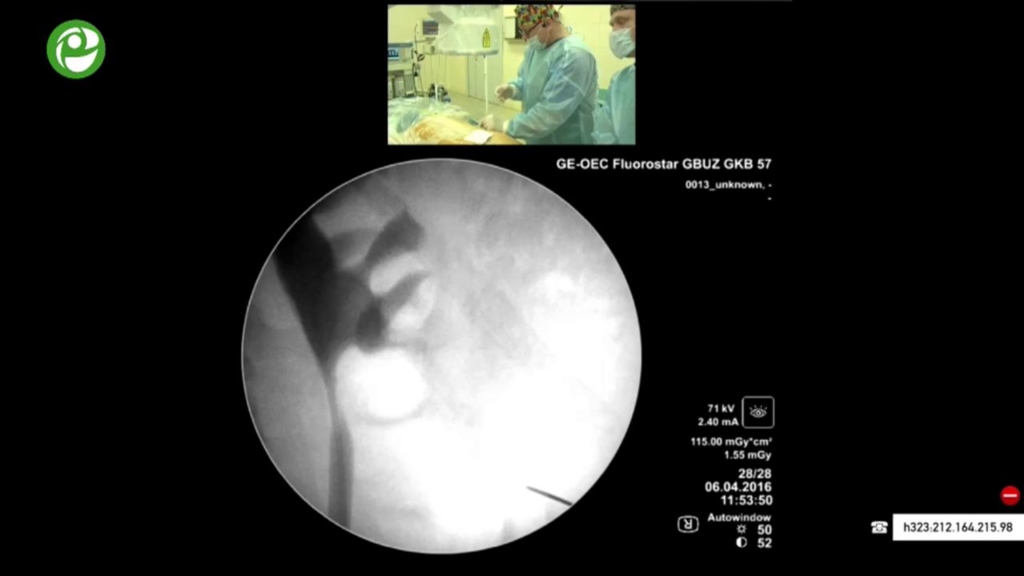

Перкутанная мининефролитотрипсия справа

04 мая 2016